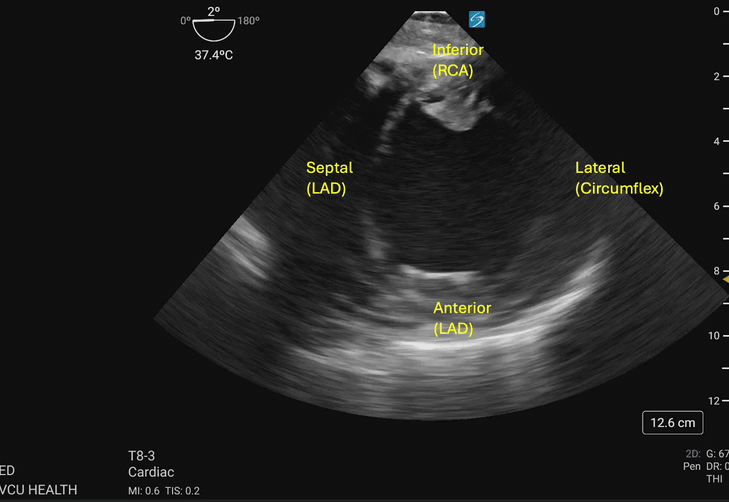

Hypokinesis or akinesis of the left ventricular myocardium segments can indicate tissue ischemia or infarction in specific vascular territories (Figures 3a and 3b). The RCA supplies the myocardium of the inferior wall of the left ventricle. On TEE, the inferior wall is located closest to the probe footprint, since the probe is coming from the stomach located inferior to the heart. The LAD supplies the myocardium of the anterior and septal portions of the left ventricle. The circumflex artery supplies the lateral portion of the left ventricular myocardium and will be shown on the rightward aspect of the ultrasound image.4

Transgastric_Figure_3a_compressed.gifFigure 3a. Walls of the left ventricle as seen on TGSAX with vascular territories. The left ventricle here demonstrates global hypokinesis rather than pathology isolated to one vascular territory. Image courtesy of Lindsay Taylor, MD.